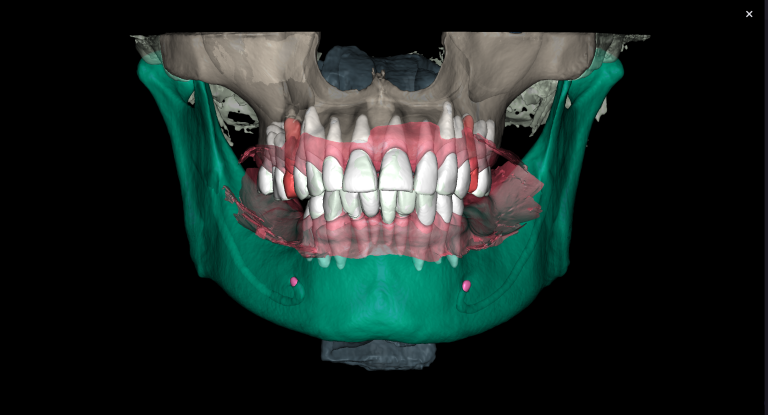

The “Third Molar Report” is a tool created by Diagnocat AI, it creates an optimal 3D visualization which helps to assess the position of the roots of the third molars relative to the roots of adjacent teeth and the floor of the maxillary sinus.

Teeth 18 (Universal 1) and 28 (Universal 16) were removed with minimal surgical trauma and without causing damage to the maxillary sinuses.